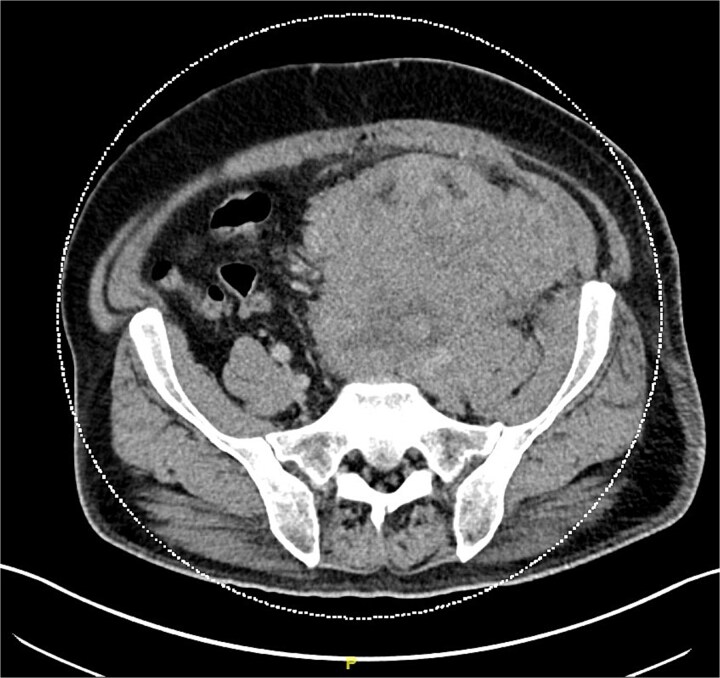

默克尔细胞癌(MCC)是一种罕见的侵袭性神经内分泌恶性肿瘤,通常出现在皮肤,并迅速进展到其他身体部位。MCC通常出现在阳光照射的区域,主要是头颈部以及上肢和肩部。它通常影响皮肤白皙的老年男性。在这个报告中,我们提出一个不寻常的MCC病例,一个48岁的白人男性,最初的表现是一个巨大的肺栓塞。患者的进一步检查显示没有典型的MCC皮肤表现,而是疾病转移。本报告的目的是强调即使患者没有常见的MCC危险因素或皮肤表现,也应将MCC视为鉴别的重要性。

Merkel cell carcinoma (MCC) is a rare aggressive neuroendocrine malignancy that typically presents in the skin and rapidly progresses to other body parts. MCC is typically found in sun-exposed areas, mainly the head and neck region as well as the upper limbs and shoulders. It typically affects fair-skinned elderly males. In this report, we present an unusual MCC case of a 48-year-old Caucasian male with an initial presentation of a massive pulmonary embolism. Further work-up of our patient indicated no typical MCC skin presentation, but rather metastases of the disease. The goal of this report is to highlight the importance of considering MCC as a differential even when patients do not present with common MCC risk factors or skin presentations.